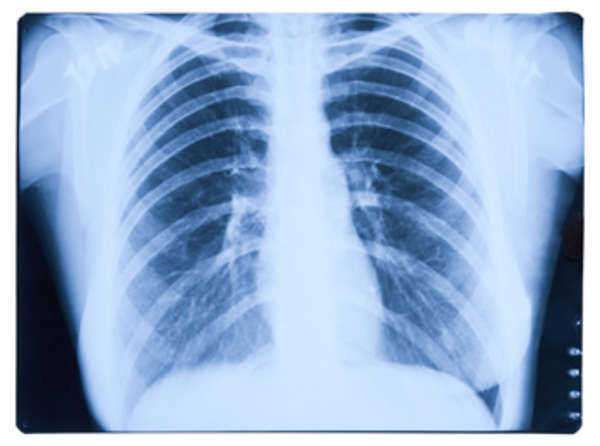

Pleural Mesothelioma Caner: As stated above, this form of mesothelioma is the most common type of mesothelioma cancer. Pleural mesothelioma cancer disrupts the lining of the lung cavity.

Mesothelioma cancer is extremely difficult to accurately diagnose because the symptoms are slow-developing. Mesothelioma cancer patients will not observe symptoms for 10-15 years following infection. Moreover, complications associated with diagnosis stem from the cellular makeup of malignant mesothelioma cancer—the disease is nearly impossible to differentiate from more basic cancers. That being said, numerous examinations and diagnostic tools are being studied and implemented to achieve a faster and more accurate mesothelioma diagnosis. One of the most common procedures associated with mesothelioma diagnosis is a Thoracoscopy.